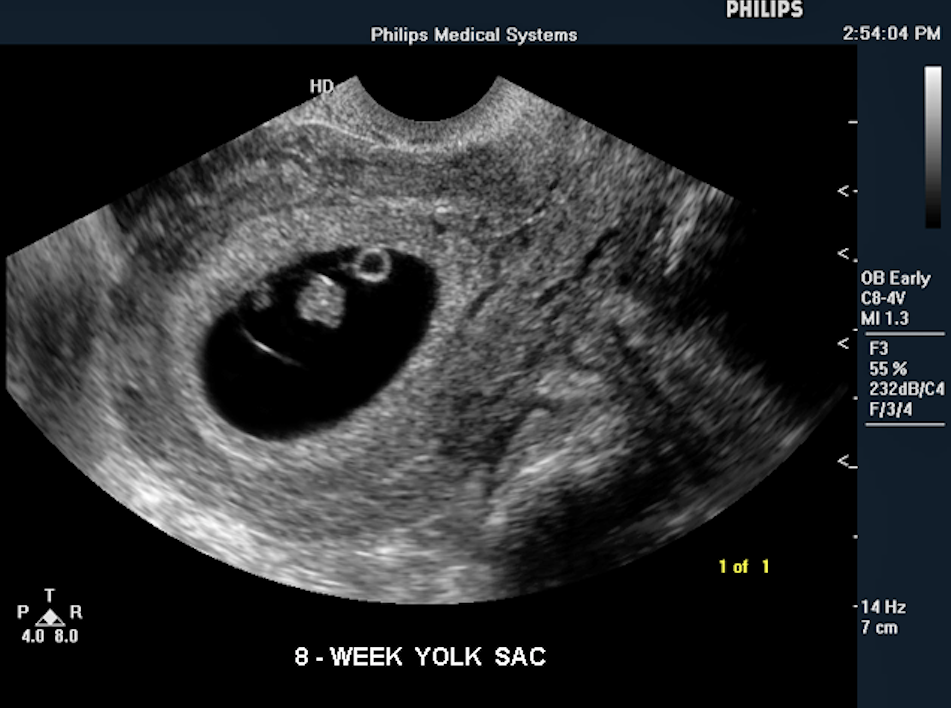

Sonogram Biometry Of Yolk Sac Biometry Of Yolk Sac In Ultrasound Ultrasound Gynecology Sonogram